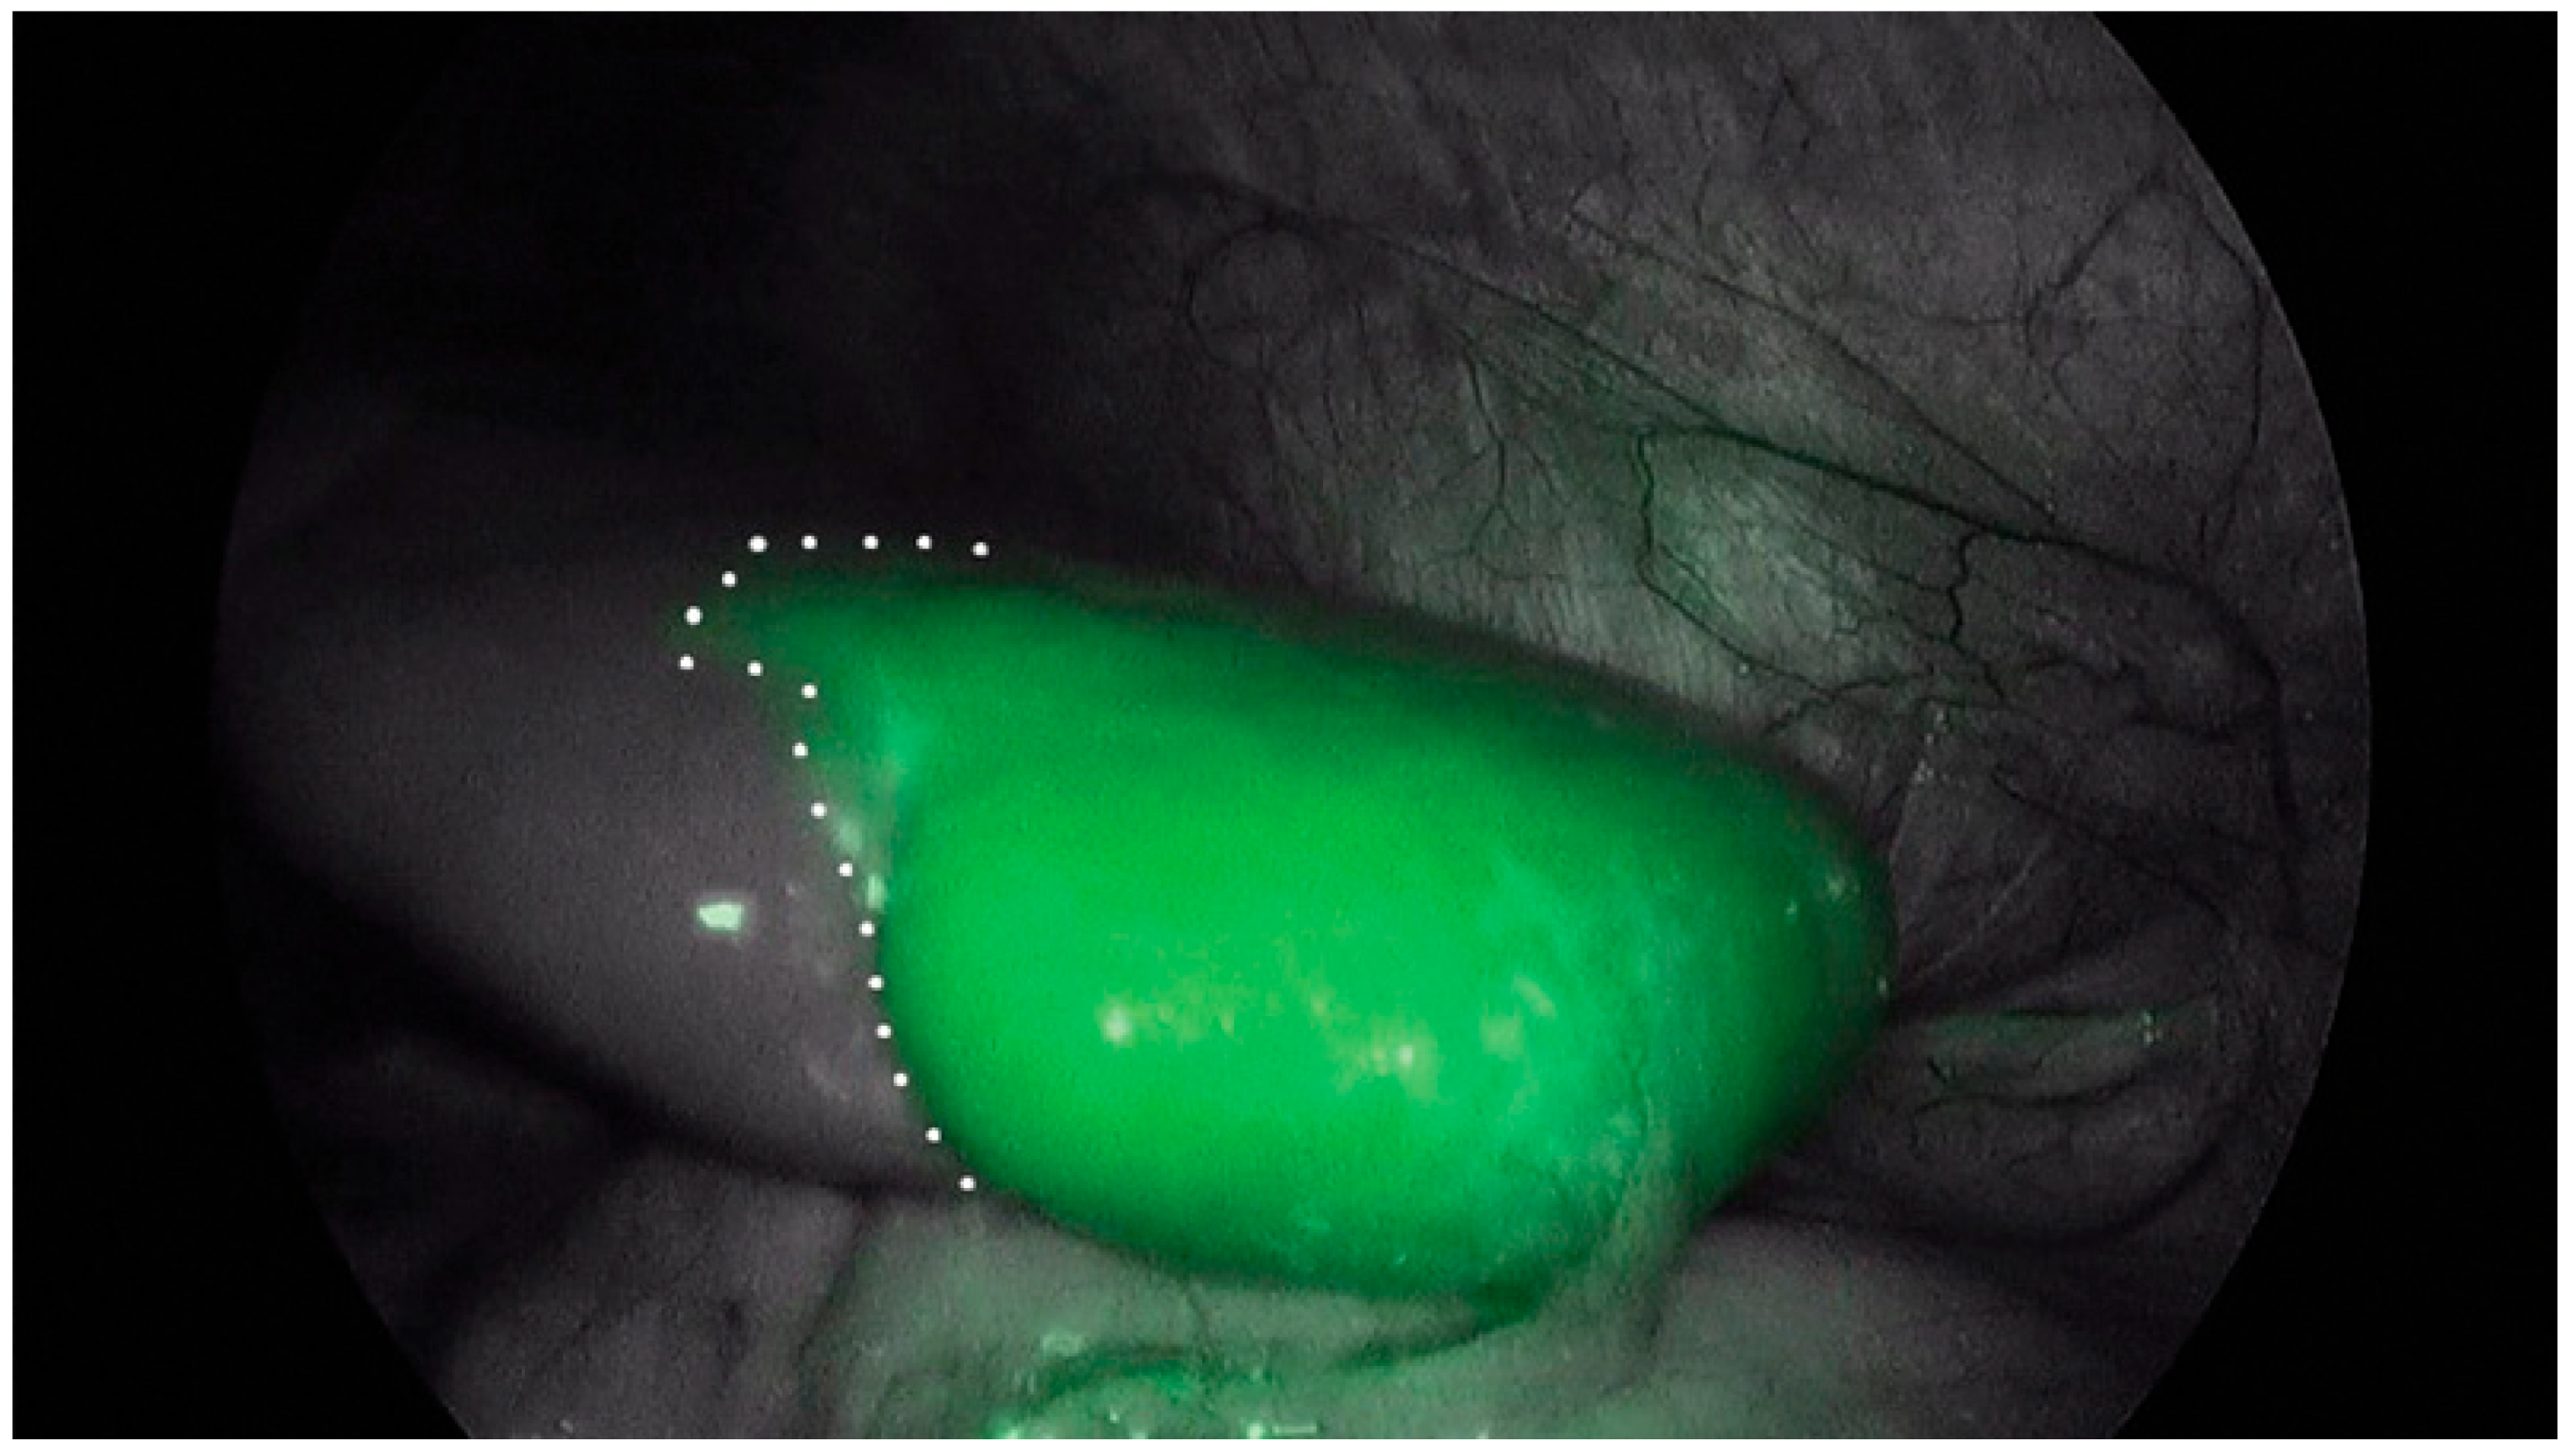

| Splenic Cysts | Intraoperatively | 0.2–0.6 mg/kg | - | - | [94,95,96] |

Funding

Institutional Review Board Statement

Informed Consent Statement

- Bada-Bosch, I.; Mata, D.P.; de la Torre, M.; Ordóñez, J.; Blanco, M.D.; de Agustin, J. Laparoscopic Partial Splenectomy Assisted by Fluorescence in a 13-Year-Old Girl. Eur. J. Pediatr. Surg. Rep. 2020, 8, e81–e85. [Google Scholar] [CrossRef] [PubMed]

- Esposito, C.; De Luca, U.; Cerulo, M.; Del Conte, F.; Bagnara, V.; Coppola, S.; Corcione, F.; Lepore, B.; Settimi, A.; Escolino, M. Twenty-Five-Year Experience with Minimally Invasive Splenectomy in Children: From Minilaparotomy to Use of Sealing Devices and Indocyanine Green Fluorescence Technology: Tips and Tricks and Technical Considerations. J. Laparoendosc. Adv. Surg. Tech. A 2022, 32, 1010–1015. [Google Scholar] [CrossRef] [PubMed]

- Masuya, R.; Nakame, K.; Tahira, K.; Kai, K.; Hamada, T.; Yano, K.; Imamura, N.; Hiyoshi, M.; Nanashima, A.; Ieiri, S. Laparoscopic dome resection for pediatric nonparasitic huge splenic cyst safely performed using indocyanine green fluorescence and percutaneous needle grasper. Asian J. Endosc. Surg. 2022, 15, 693–696. [Google Scholar] [CrossRef] [PubMed]